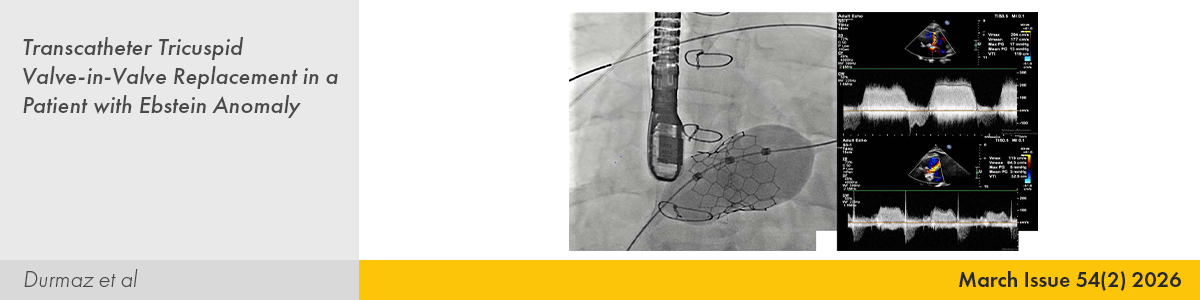

| CASE IMAGE | |